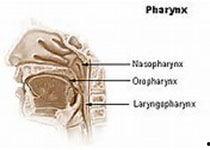

首先,得先弄清楚什么是鼻饲管。简单来说,鼻饲管是一种用于将食物、药物或营养液直接送入胃部的管道。它通常由硅胶或聚氯乙烯等材料制成,柔软且具有一定的弹性。这种管子通过鼻腔插入,直达胃部,对于无法正常进食的患者来说,简直就是救星。

那么,问题来了,为什么我们要测量鼻饲管的长度呢?这主要是因为鼻饲管的长度直接关系到它能否正确到达胃部。如果长度不够,食物或药物可能停留在食管或胃的上部,导致患者不适甚至窒息;如果长度过长,可能会损伤胃壁或肠道。

2. 测量鼻尖到耳垂的距离:将测量尺紧贴鼻尖,沿着鼻梁一直延伸到耳垂,记录下这个距离。

3. 测量耳垂到剑突的距离:将测量尺从耳垂处垂直向下,直到剑突,再次记录下这个距离。

4. 计算总长度:将鼻尖到耳垂的距离和耳垂到剑突的距离相加,得到鼻饲管的总长度。